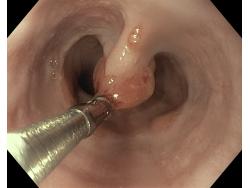

Polipy